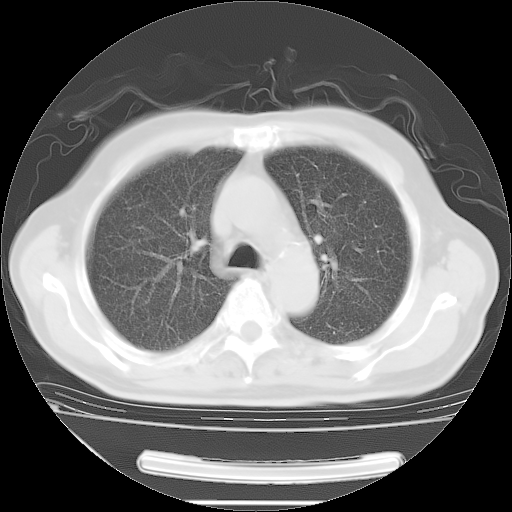

今天复查肺部CT,发现双肺广泛磨玻璃样改变。所以我把3月19日和5月9日相隔50天的肺部CT上传。请大家会诊。

5月9日肺部CT(在4月27日齐鲁医院肺部CT描述部分肺组织磨玻璃样改变,12天后肺组织广泛磨玻璃样改变)

大致读了系列胸部CT:纵隔窗无明显异常,肺窗:从4、27至今:主要是双肺中下野外带可见毛玻璃样改变,目前处于急性肺泡炎阶段,至于原因考虑1、结替组织或胶原血管性疾病所致?2、恶性疾病如恶组在肺部所致的表现或细支气管肺泡癌?3、药物或其它原因如肺蛋白沉着症所致肺泡炎目前不太可能?总之,明天就去请我院的呼吸科、感染科、血液科和临免专家会诊哈。